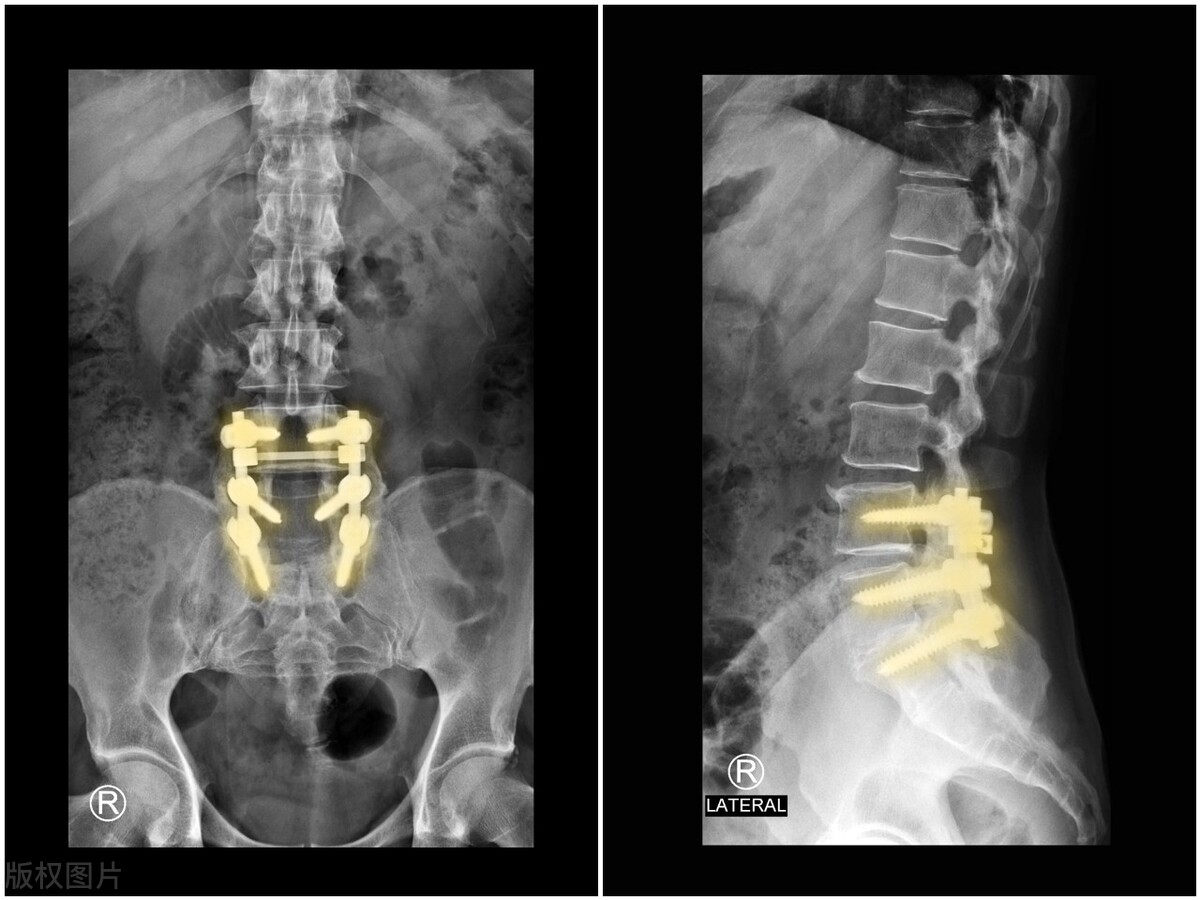

通过调理整体气血通畅,调节脏腑功能和整体平衡,激发修复能力,同时配合消炎镇痛的药物,来改善休息质量,使身体进入健康良性循环。

虽然突出的椎间盘一般不能回纳,狭窄的腰椎管不能自愈,但可以延缓、避免骨质增生和局部肿胀,避免症状加重和复发。同时随着年龄的增长,椎间盘水分越来越少,突出的部分会慢慢萎缩,也会减轻症状复发的可能。因此通过汤药来整体调理,配合康复训练,培养养腰护腰的习惯,是完全可以解决腰椎管狭窄问题的。